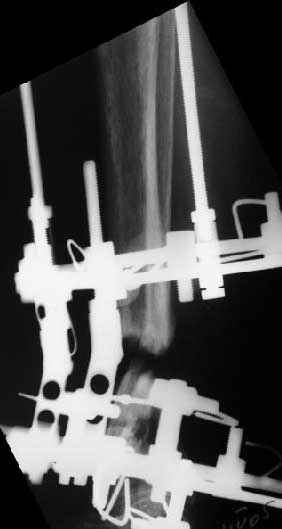

Глубокоуважаемые коллеги,Поступила женщина 72 лет. Полтора года назад - укушенная рана, перелом голени. Лечили аппаратом, не срослось. Долго не заживала рана.

Но вроде уже с полгода мягкие ткани закрыты. Спереди подпаянные рубцы. Есть приличная подвижность на уровне несращения. Картинки в приложении. Что предложите? Спсибо заранее.

В общем, начали c аппарата - нложили, малоберцовую внизу пересекли, выбрали люфт, раз дальше сопротивление пошло - выведем постепенно.

Картинки приложены. Жду комментариев.